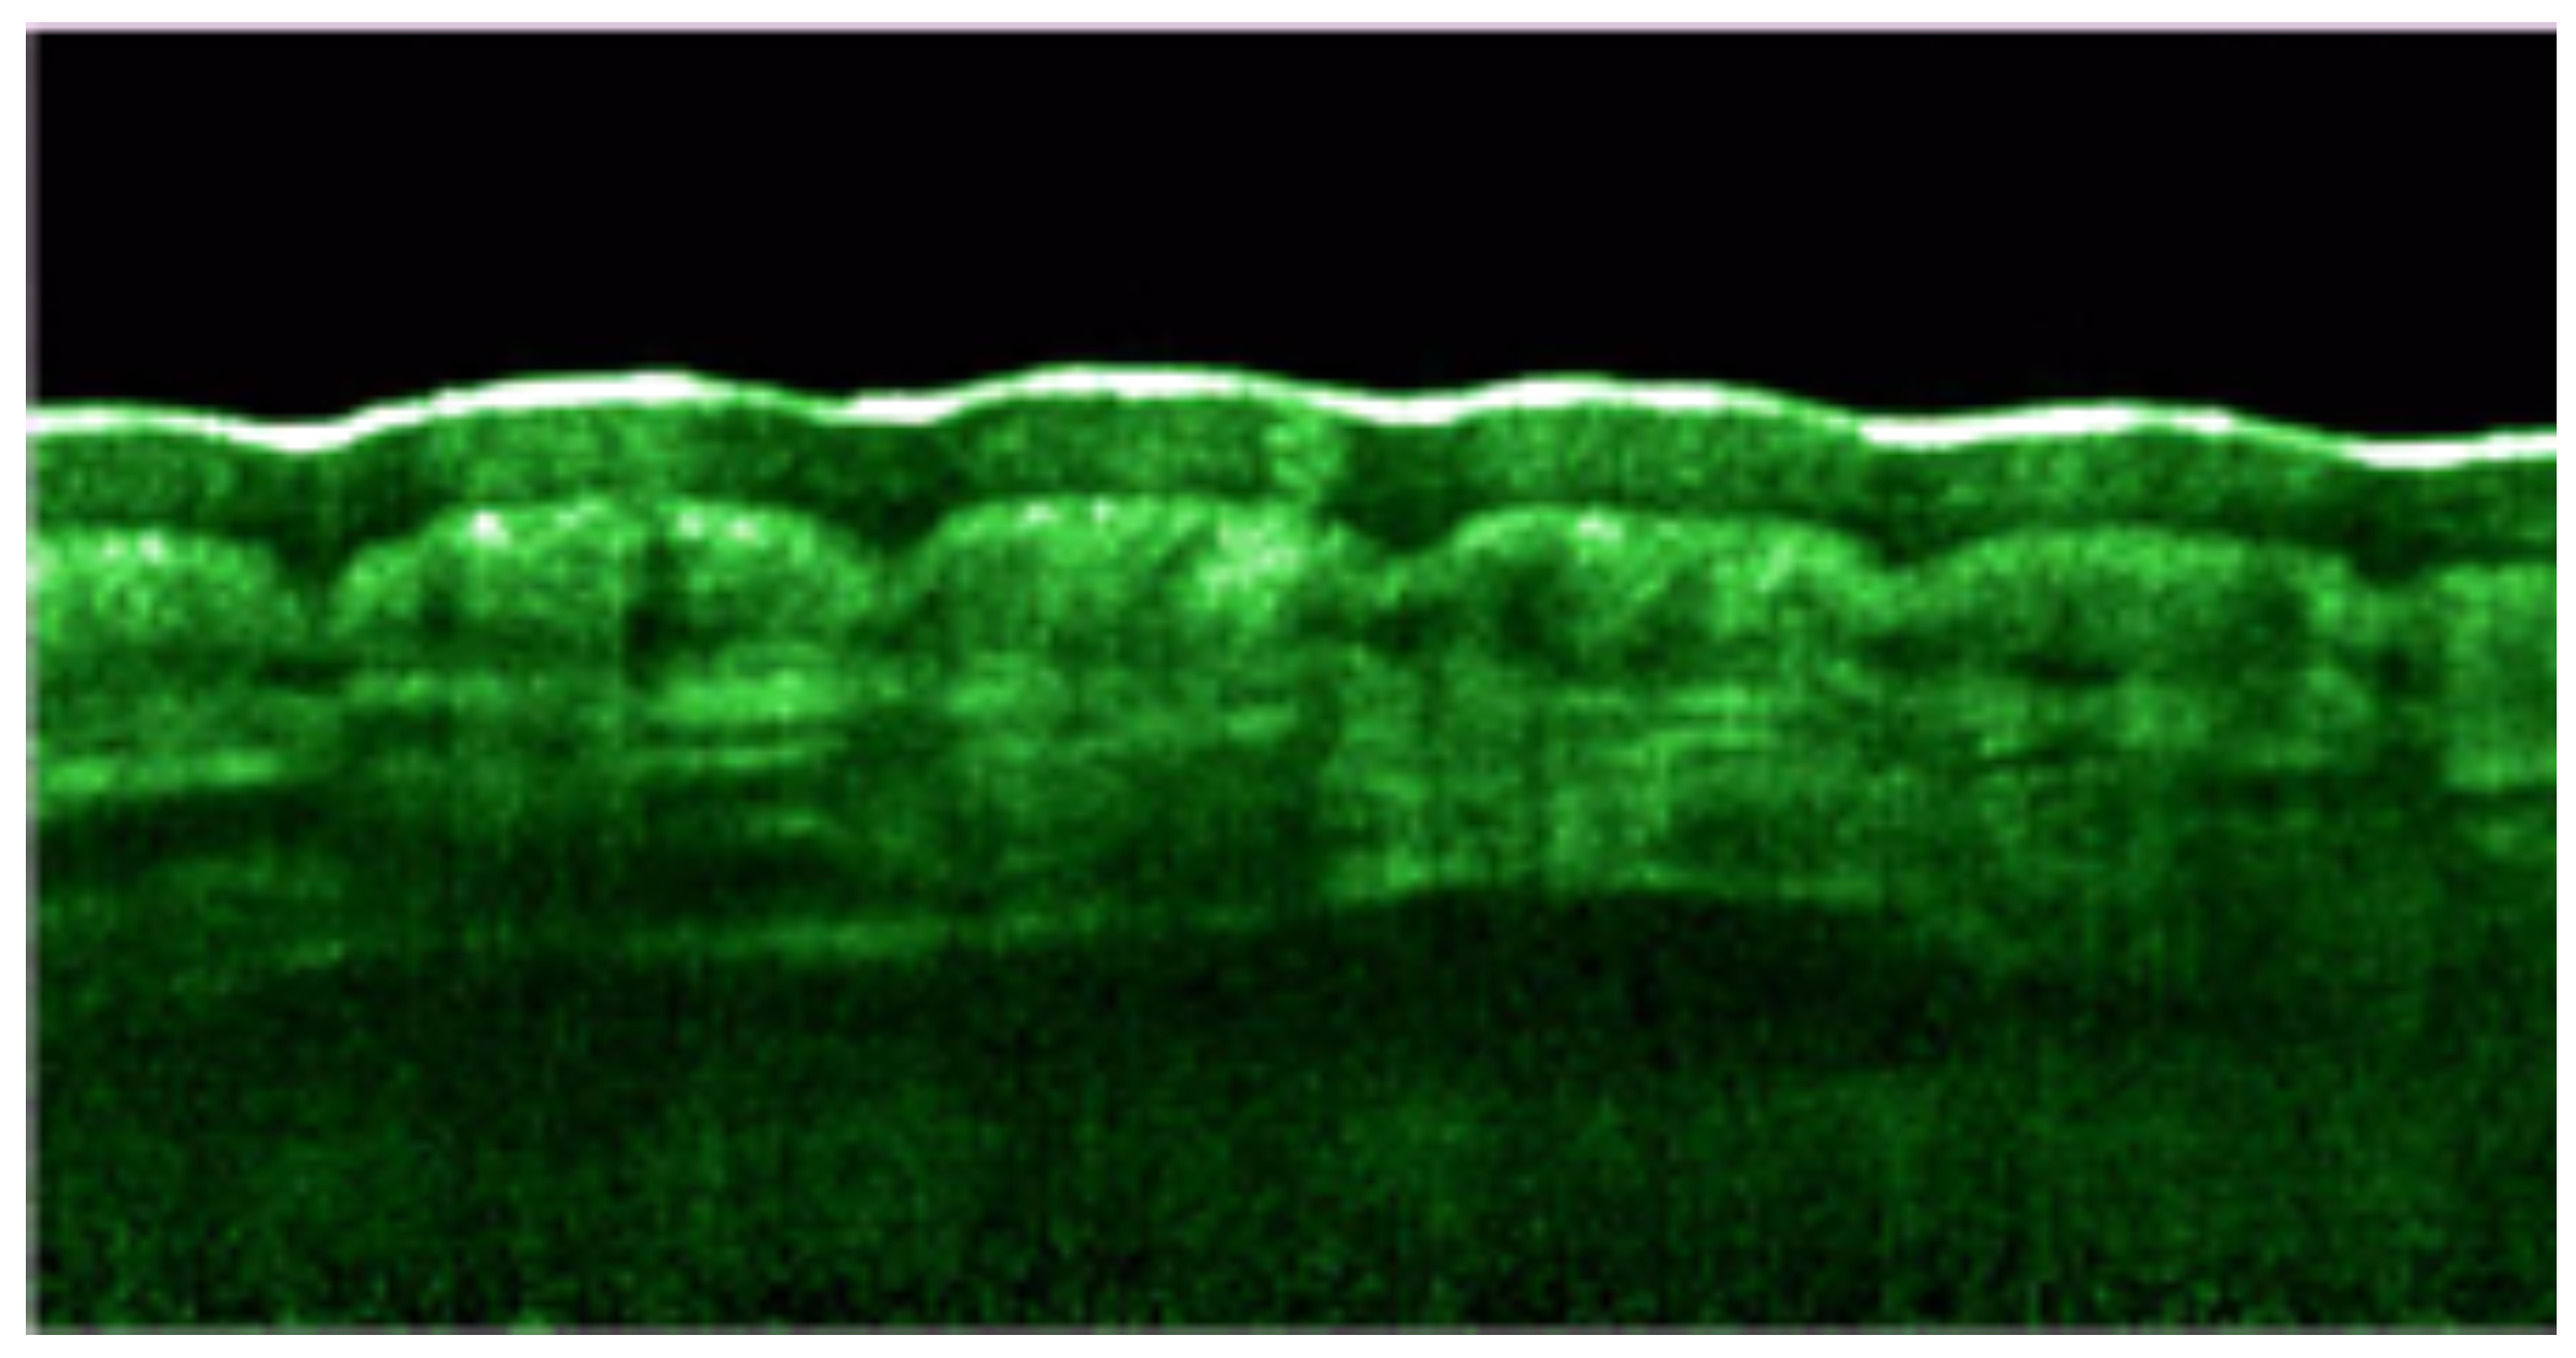

9. Optical Coherence Tomography

- Welzel, J.; Bruhns, M.; Wolff, H. Optical coherence tomography in contact dermatitis and psoriasis. Arch. Dermatol. Res. 2003, 295, 50–55. [Google Scholar] [CrossRef]

- Mogensen, M.; Morsy, H.; Thrane, L.; Jemec, G. Morphology and epidermal thickness of normal skin imaged by optical coherence tomography. Dermatology 2008, 217, 14–20. [Google Scholar] [CrossRef]

- Welzel, J.; Lankenau, E.; Birngruber, R.; Engelhardt, R. Optical coherence tomography of the human skin. J. Am. Acad. Dermatol. 1997, 37, 958–963. [Google Scholar] [CrossRef]

- Mogensen, M.; Thrane, L.; Joergensen, T.; Andersen, P.; Jemec, G. Optical Coherence Tomography for Imageing of Skin and Skin Diseases. Semin. Cutan. Med. Surg. 2009, 28, 196–202. [Google Scholar] [CrossRef] [PubMed]